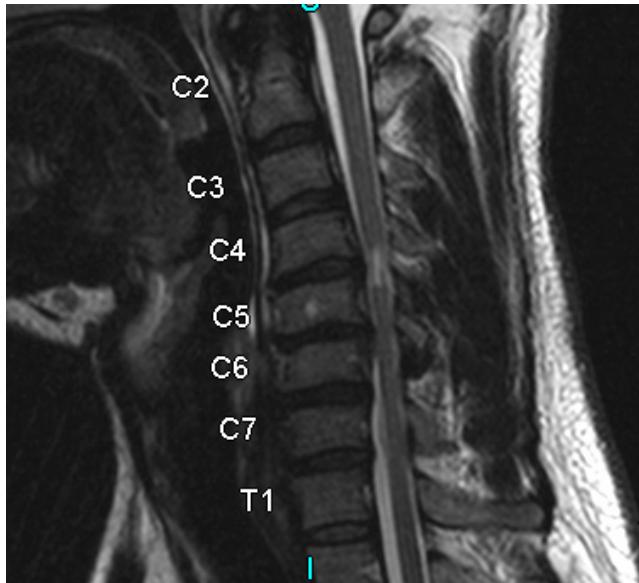

Cervical MyelopathyZ

- Definition: Common form of neurologic impairment caused by compression of cervical spinal cord, most commonly due to degenerative cervical spondylosis

- Typical presentation: Older patients with symmetric numbness and tingling in extremities, hand clumsiness, and gait imbalance

- Treatment: Usually surgical decompression and stabilization as condition is associated with step-wise progression

Imaging:

- MRI: Study of choice to evaluate degree of spinal cord and nerve root compression

Imaging Examples:

Surgical Treatment - Anterior Cervical Discectomy and Fusion: